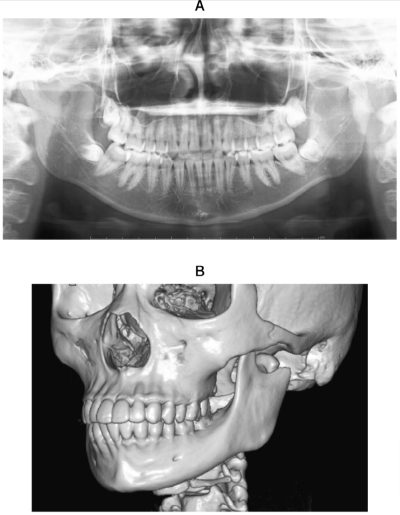

22歳の女性。開口障害を主訴として来院した。交通事故に遭遇して顔面を強打したという。観血的に治療を行うこととした。初診時のエックス線画像と3D-CT、下顎骨下縁を矢印で示した術中写真及び術後の頭部後前方向エックス線写真を別に示す。

術後に起こりやすい合併症はどれか。1つ選べ。